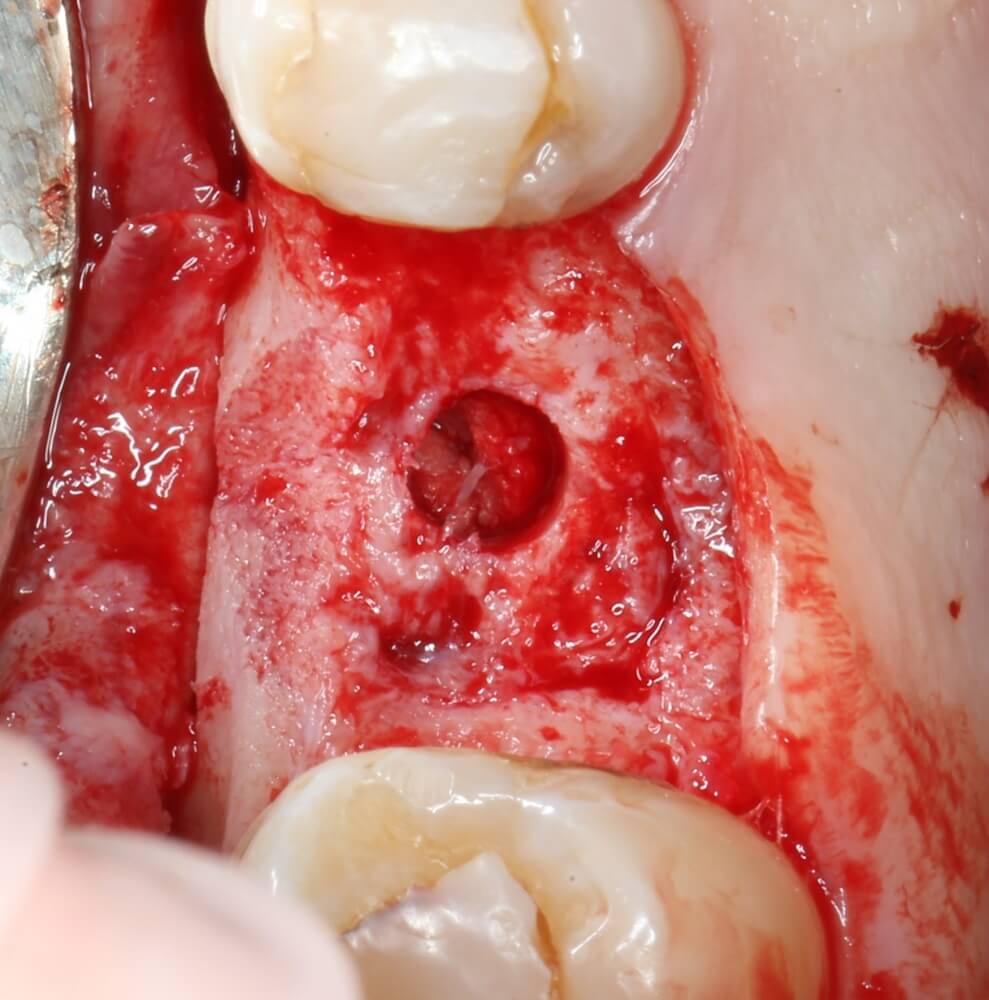

После этого можно еще раз (последний, кстати), проверить направление и ангуляцию оси будущего имплантата. Всё тем же вышеозначенным пином:

Если бы мы хотели поставить имплантат диаметром 4.5 мм, то далее мы перешли бы к кортикальной конической фрезе. Однако ж, я посчитал, имплантат диаметром 5.0 мм в данной клинической ситуации будет более надежным и органичным, поэтому мы продолжаем подготовку лунки. И следующая используемая фреза — 3.2/3.7 — то же самое. что и предыдущая, с направляющей 3.2 мм:

Это — финишная фреза при подготовке лунки под имплантат диаметром 5.0 мм (за исключением Osseospeed S, т. е. с цилиндрической шейкой). Но лунка под имплантат еще не готова. Давайте еще раз посмотрим на имплантат, который мы собираемся установить:

То есть, конкретно у этого имплантата между диаметром тела (3.7 мм) и диаметром платформы (5.0 мм) есть существенная разница. Это, кстати, нередко вводит в заблуждение имплантологов, впервые столкнувшихся с этой имплантационной системой — не совсем понятно, как таким набором фрез подготовить лунку под такой большой имплантат.

В общем, мы с вами не придурки слесари-столяры, периимплантита не хотим, поэтому кортикальные фрезы не игнорируем:

Кортикальная фреза погружается строго до отметки (см выше). В нашем клиническом случае (с синуслифтингом) это особенно важно, чтобы имплантат не улетел в субантральное пространство. Таким образом получаем лунку, полностью конгруэнтную будущему имплантату. Это очень-очень важно: